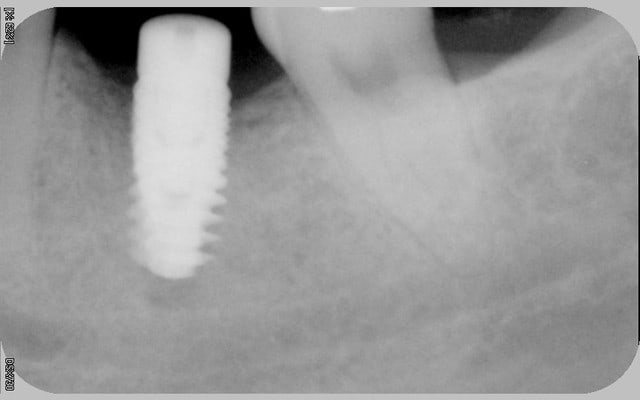

tous mes implants sont ostéo-intégrés, mais je trouve que la cratérisation est très importante et surtout très rapide.

donc pour moi, il y a un problème même si le taux de succès est de 100% en 2 ans.

voici les radios le jour de la pose

le krestal doit être en crestal et non en infra-osseux: il s'agit d'une connectique à plat et non d'un cône morse.

Mais je penses sérieusement que le problème vient de la connectique qui n'est pas adapté à une position juxta-crestale.

Suffit de voir si quelqu'un a eu les mêmes problème avec l'in-kone et on sera fixé, vu que c'est le même implant, y a que la connectique qui change.